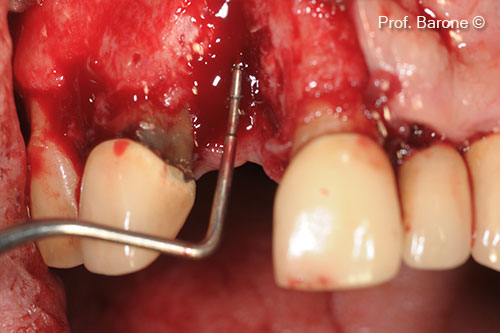

Buccal View, tooth #11

Residual Bone Defect, mesio-distal dimension

: Residual Bone Defect, vertical dimension